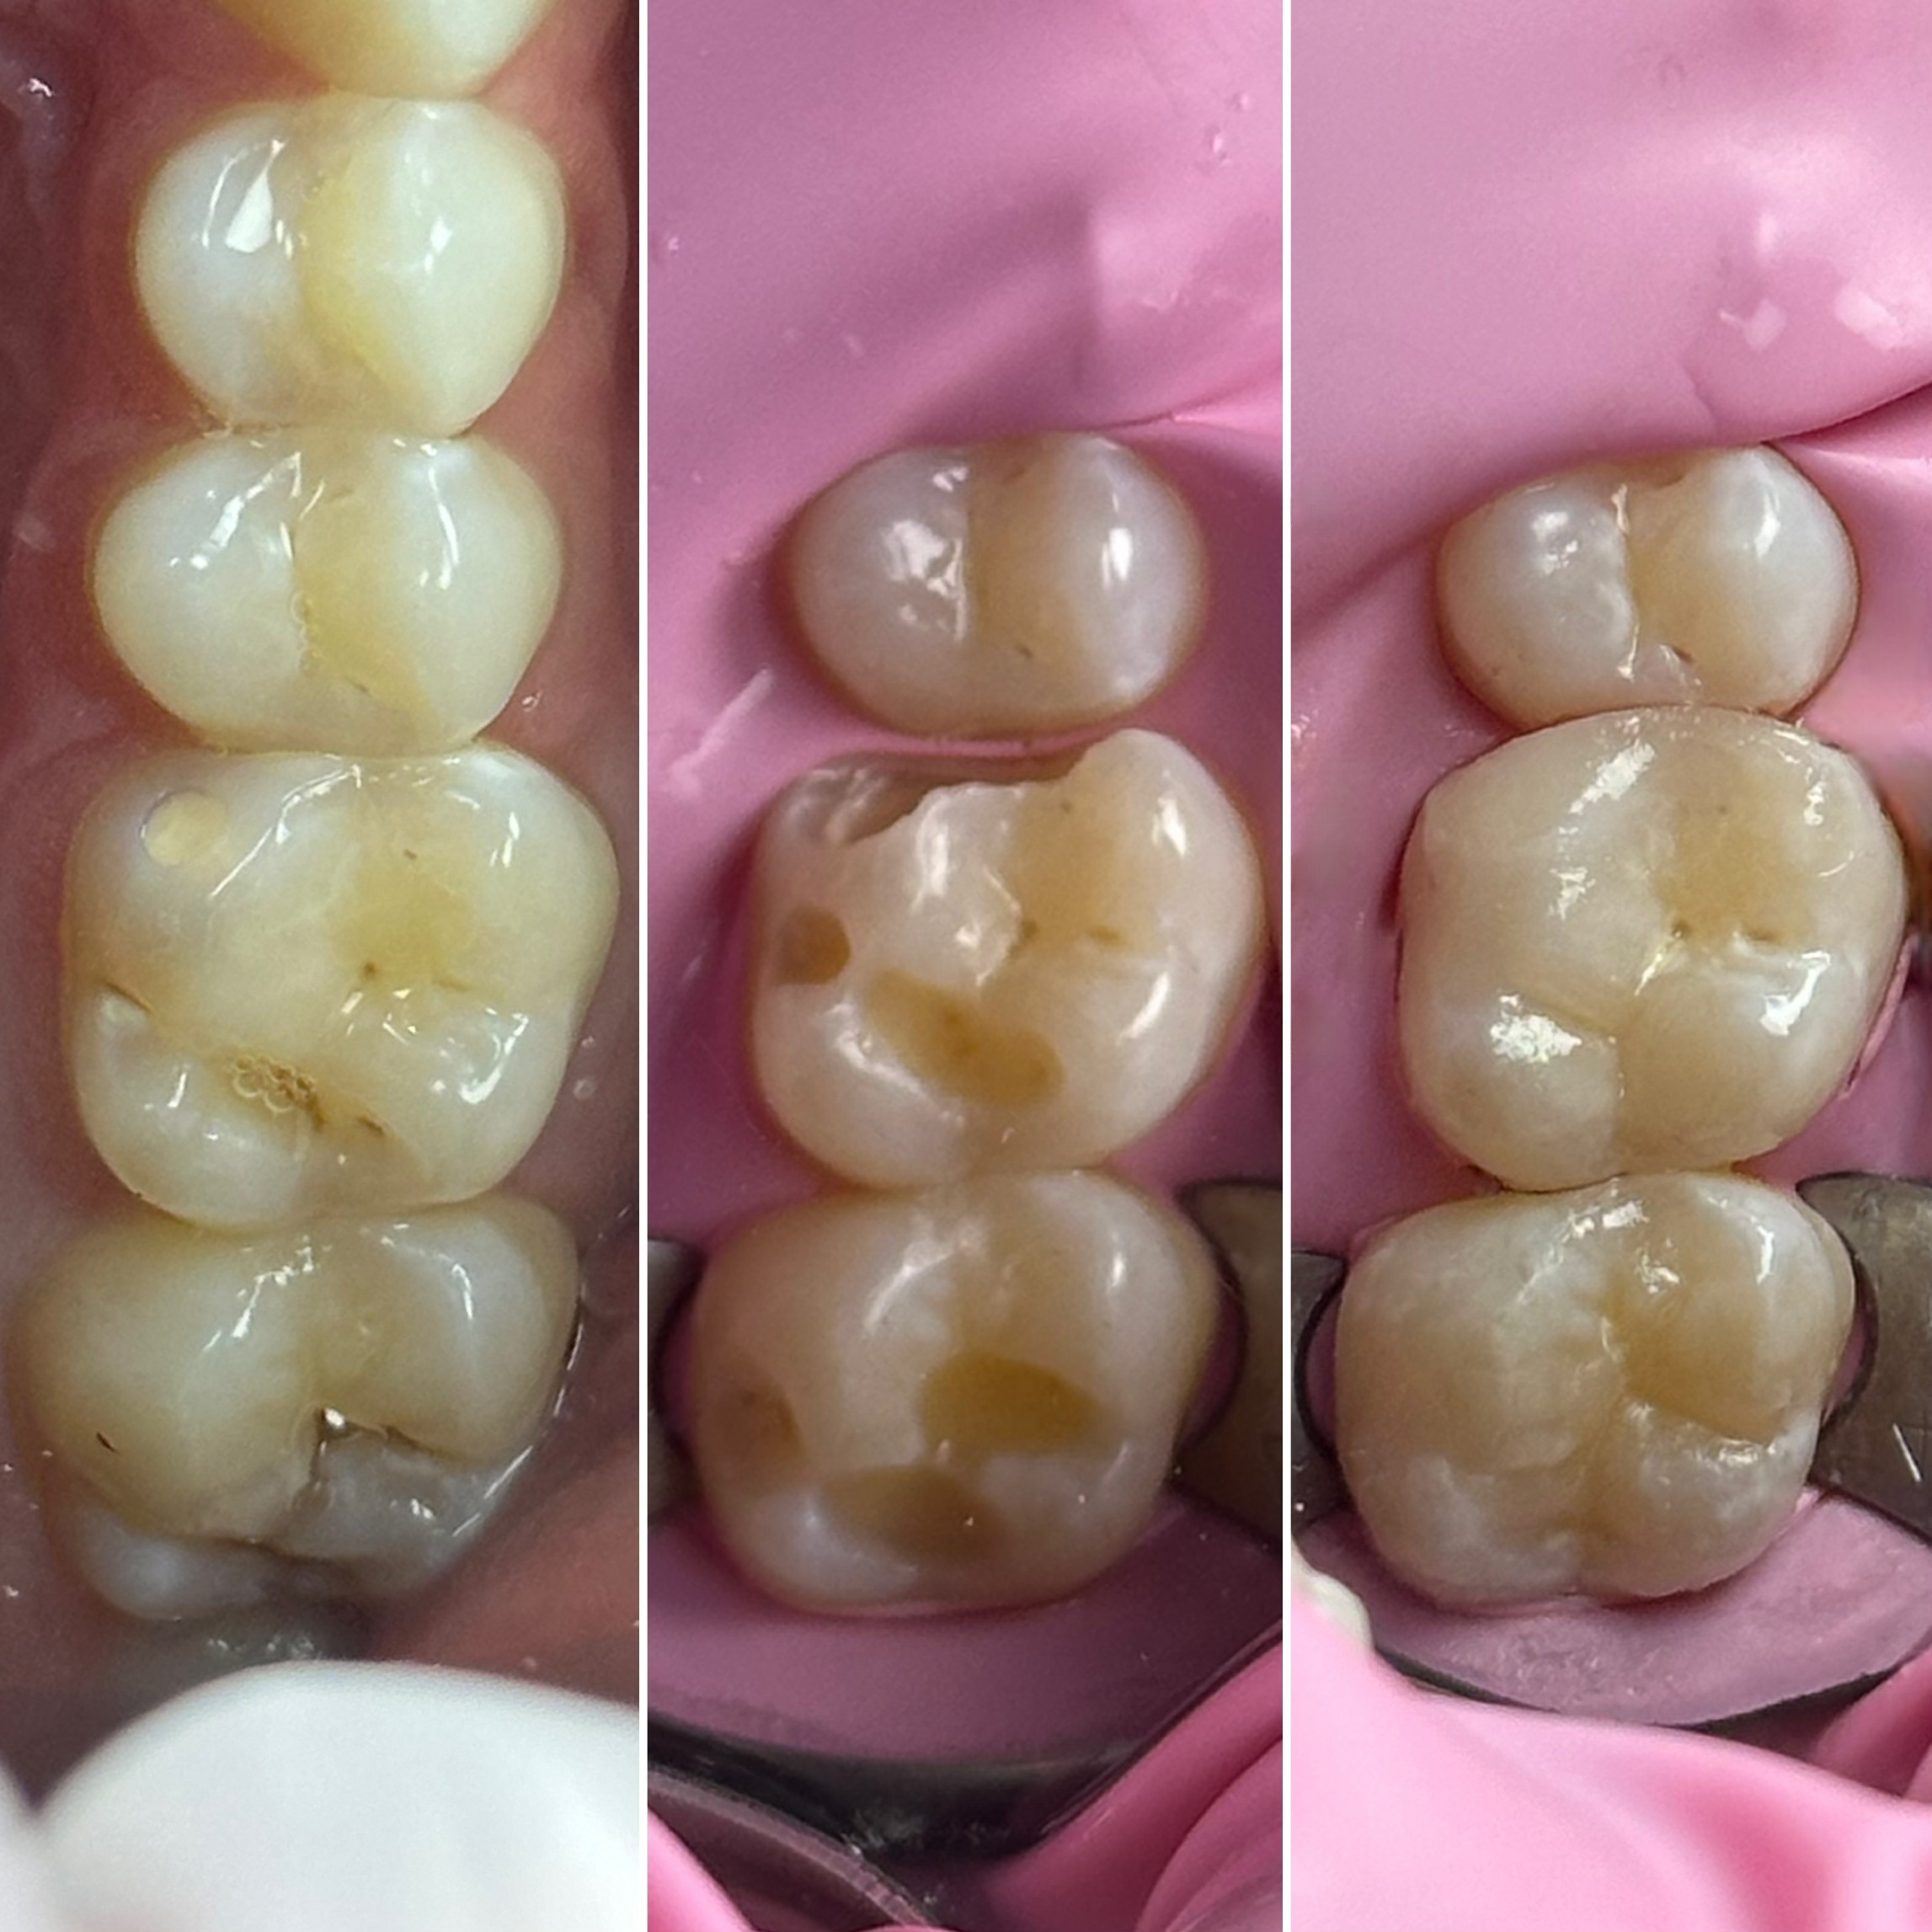

• Художественная реставрация фронтального и бокового участка зубов

2022 год – «Прямая реставрация.Боковой сегмент.» Игорь Гудыма